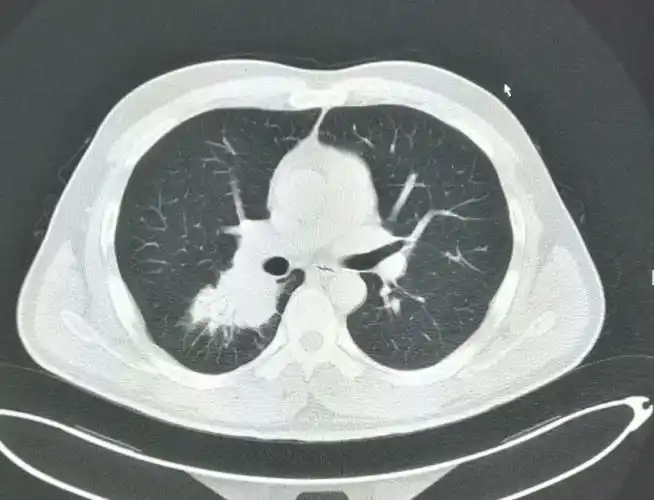

典型的肺癌